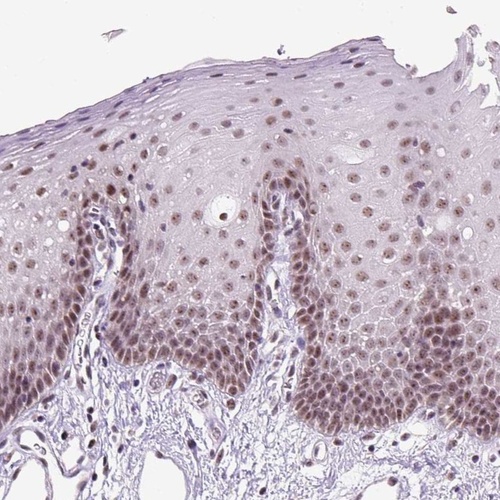

Immunohistochemical staining of human oral mucosa shows nuclear positivity in squamous epithelial cells.